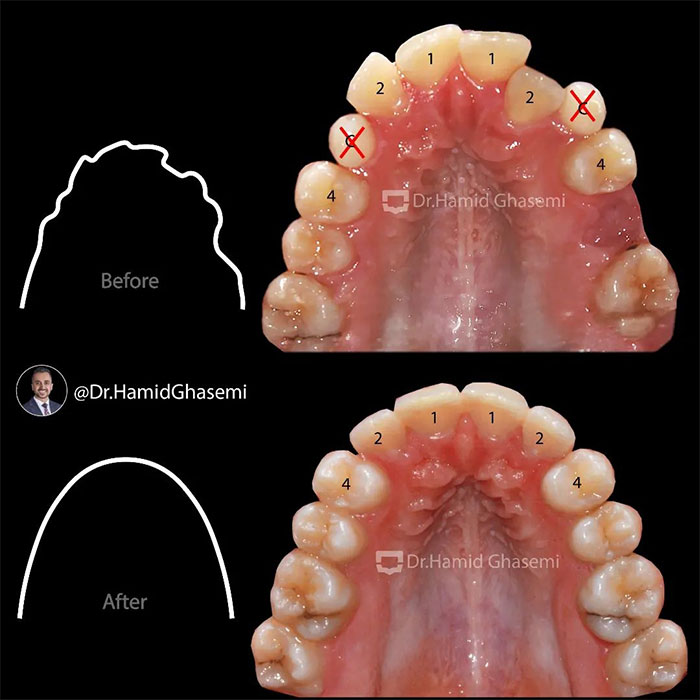

یک کیس خیلی جالب با مشکل جلوزدگی متوسط فک بالا و پایین (Bimaxillary dentoalveolar protrusion ) همراه با نهفتگی دوطرفه دندانهای نیش فک بالا. درمان با کشیدن دندان های نیش نهفته فک بالا و دندانهای پرمولر اول پایین انجام شد. تغییرات مثبت و قابل توجه در پروفایل و حالت لبهای بیمار پس از درمان و کسب اکلوژن کلاس ۱ ایده آل همچنان که دندانهای پرمولر اول بالا جایگزین دندانهای نیش نهفته در فک بالا شدند کاملا مشهود است.

This was such an amazing case with moderate bimaxillary dentoalveolar protrusion plus impacted bilateral upper canines. The case was treated by extraction of upper impacted canines and lower 1st premolars. Significant profile change achieved while upper 1st premolars substituted for upper canines properly with a solid perfect class 1 dental occlusion.